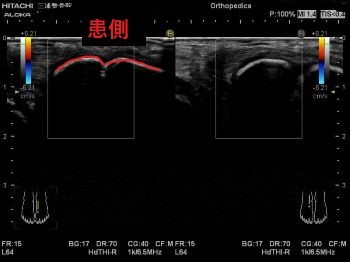

エコーではこのように写ります。

患側では大きく腫れて

正常な靭帯線維が見えないため

二分靭帯が断裂しています。

エコーの良い所として

動かしながらも観れるので

関節がどのくらいぐらついているかなども

判断できます。